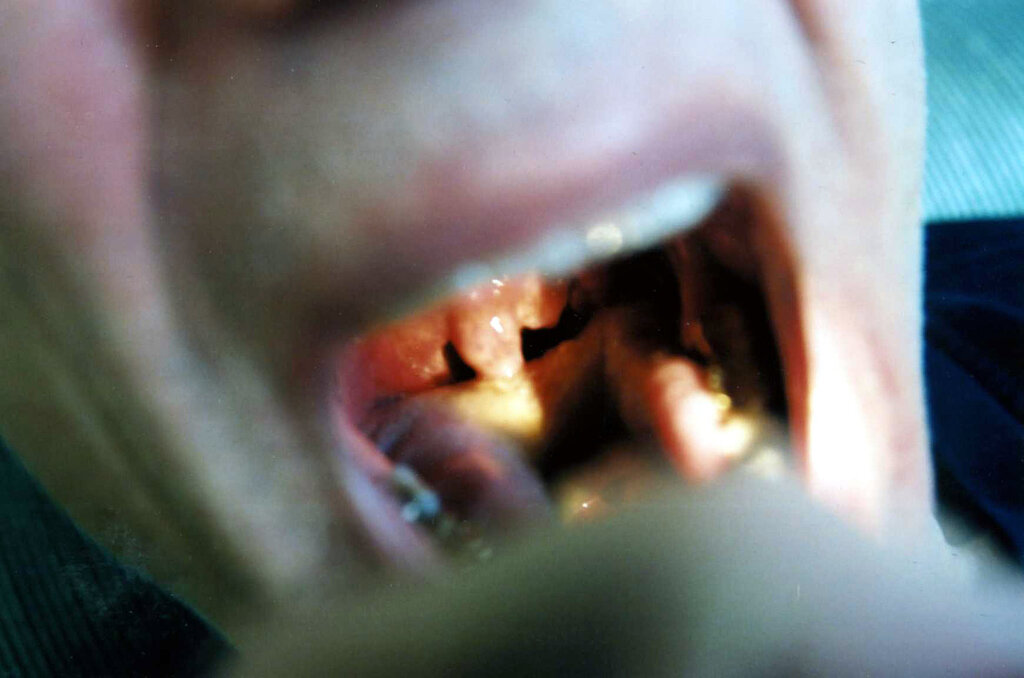

HPV Is Causing a Rapid Increase in Throat Cancer

Over the past 20 years, there has been a rise in throat cancer cases in the United States and the United Kingdom. Many health experts are blaming this on a sexually transmitted disease called human papillomavirus (HPV). Specifically, the type of throat cancer being dubbed an “epidemic” is called oropharyngeal cancer. This affects the area of the tonsils and the back of the throat.

Like cervical cancer, oropharyngeal cancer is caused by HPV. Human papillomavirus is a sexually transmitted disease that is transmitted through intimate skin-to-skin contact. Over 42 million Americans are infected with a type of human papillomavirus — there are over 100 different kinds. However, not all of them cause health problems. This means that people could be walking around with a type of HPV and not realize it.

About 70% of throat cancer is caused by HPV, according to Dr. Hisham Mehanna, from the UK’s University of Birmingham. Furthermore, those who have multiple oral sex partners are nine times more likely to get throat cancer.

throat cancerThe Centers for Disease Control and Prevention (CDC) recommend children should receive their first HPV vaccine before the age of 15. They will need one more dose after that. Those who receive the first dose on or after their 15th birthday will need a total of three doses. The vaccine doses are most effective when it is given before a person is exposed to HPV.

However, only 54% of all Americans receive the HPV vaccine. This is way below the 80% figure believed to keep the population safe.

For example, HPV and oropharyngeal cancer can be contracted by any sex or pronoun. Furthermore, the rise in throat cancer has risen by about 1% in women and roughly 3% in men.

Roughly 54,540 new cases of oral cavity or oropharyngeal cancer have been diagnosed in the U.S. as of 2023. Additionally, there have been about 11,580 deaths reported from these causes, according to the American Cancer Society.

Top and Featured Image Courtesy of Stephanie Young Merzel‘s Flickr Page – Creative Commons License